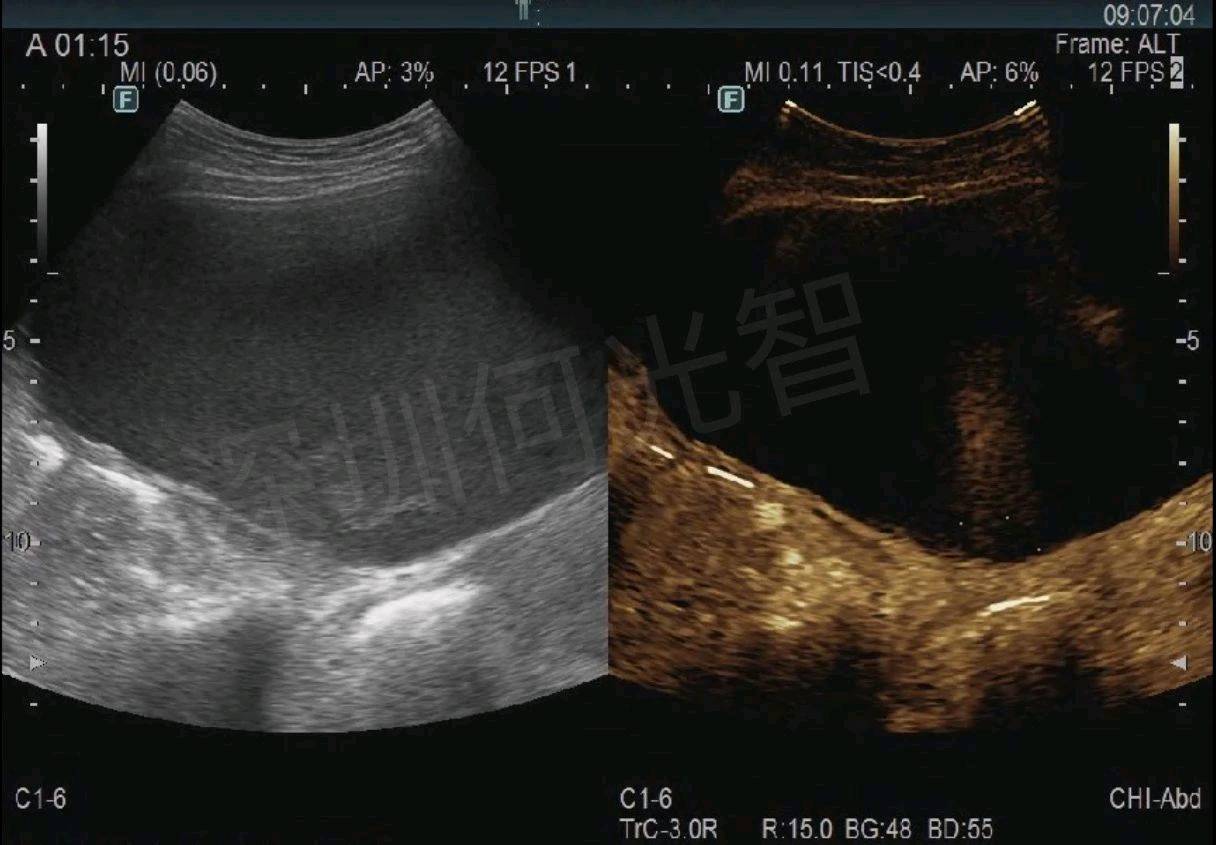

图1.2超声显示盆腔巨大囊性包块,内可见密集细弱点状回声,超声造影显示囊壁未见强化结节。